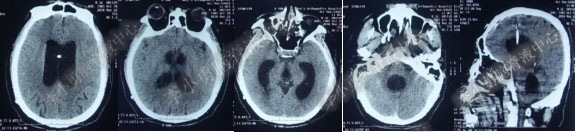

第4次出院后11天即2018年4月15日(分流术后284天,第2次的软性内镜术后179天),因引流管堵塞第5次住入该院,引流管内白色絮状物增多,引流管被堵塞。入院当天复查头部CT(图-10)显示脑室系统仍扩张。

图-10:2018年4月15日头部CT

第5次入院第2天即2018年4月17日,脑室腹壁外引流管堵塞,意识恶化,复查头部CT(图-11)示全脑室系统又较前扩大。当天急诊行左侧脑室穿刺外引流术。脑脊液化验外观黄色浑浊,并且送培养,结果是无菌生长。

图-11:2018年4月17日头部CT脑室扩张又加重

第5次入院第3天即2018年4月18日术后复查头部CT(图-12)显示脑室系统扩张较前好转。

图-12:2018年4月18日头部CT